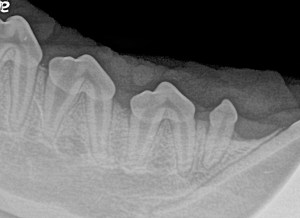

Feline Full Mouth Radiograph example